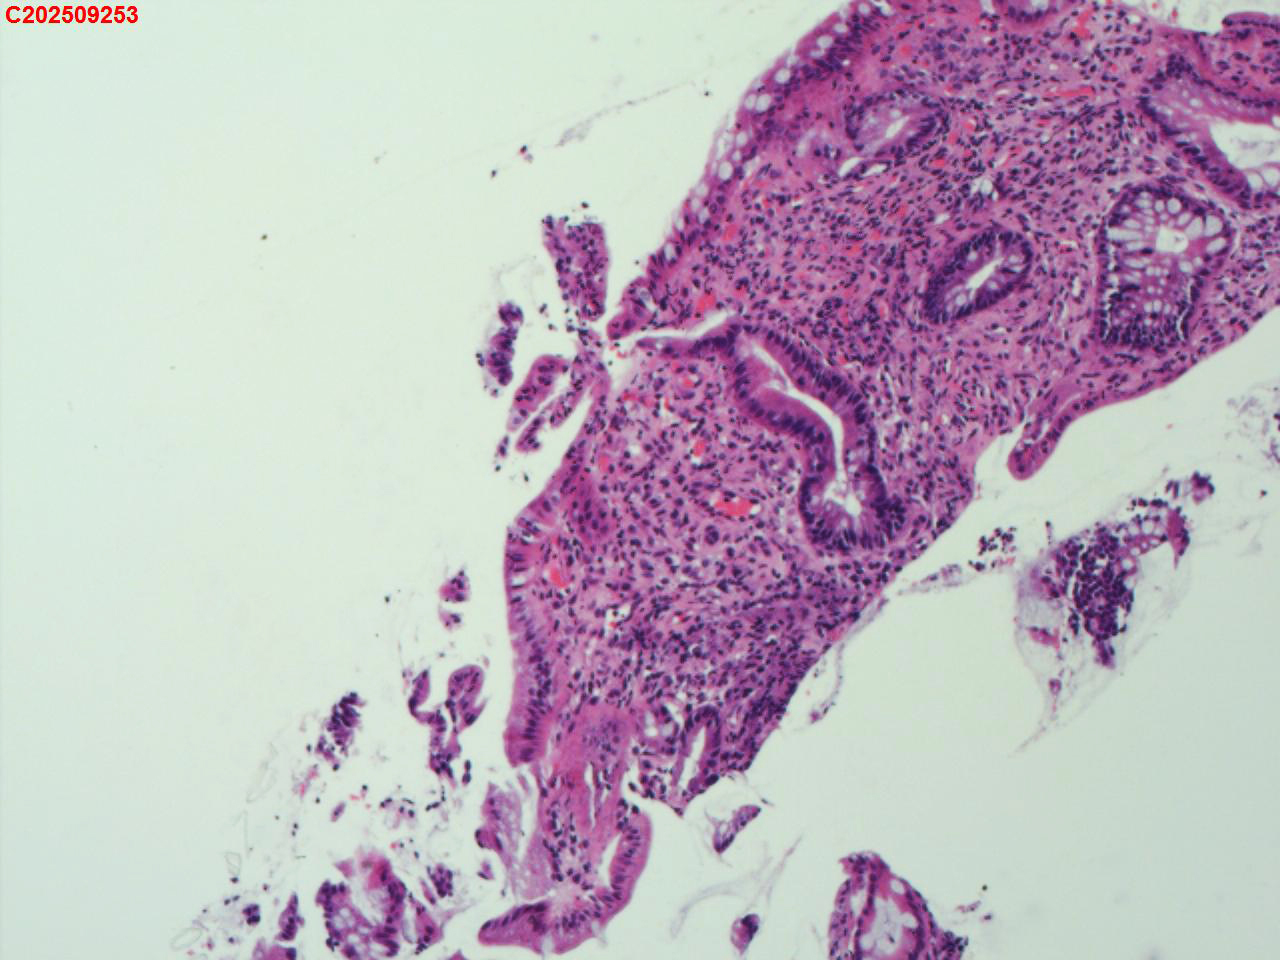

降结肠粘膜

性别

男

年龄

52岁

临床诊断

溃疡性结肠炎

一般病史

溃疡性结肠炎病史3年

标本名称

大体所见

降结肠多发鹅卵石样改变,多发糜烂。

图1